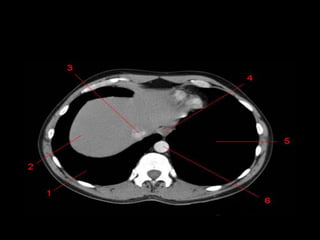

Mediastino Posterior

• Esôfago, aorta descendente, veias ázigo e

hemiázigo, ducto torácico e nervos

intercostais e autônomos.

Esôfago

• Posterior ou póstero-lateral à traquéia

• Lobos direito e esquerdo do pulmão se tocam

atrás do esôfago criando a Linha de Junção

Posterior.

• Antero-medial à aorta descendente

Sistema Azigo

• Ázigo: D

• Hemiázigo: E

– Se une em T9

• Póstero-lateral em relação a aorta

descendente.

• A veia ázigo curva-se sobre a face superior da

raiz do pulmão direito para se unir a VCS